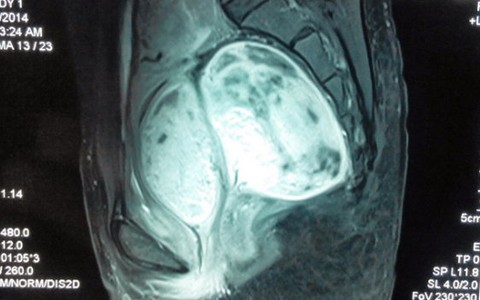

TTO - Ngày 28-4, các bác sĩ tại bệnh viện Ung thư Đà Nẵng cho biết đã mổ thành công khối u lớn trước xương cùng cụt cho bệnh nhân H.T.T.M. (36 tuổi, trú huyện Thăng Bình, Quảng Nam).